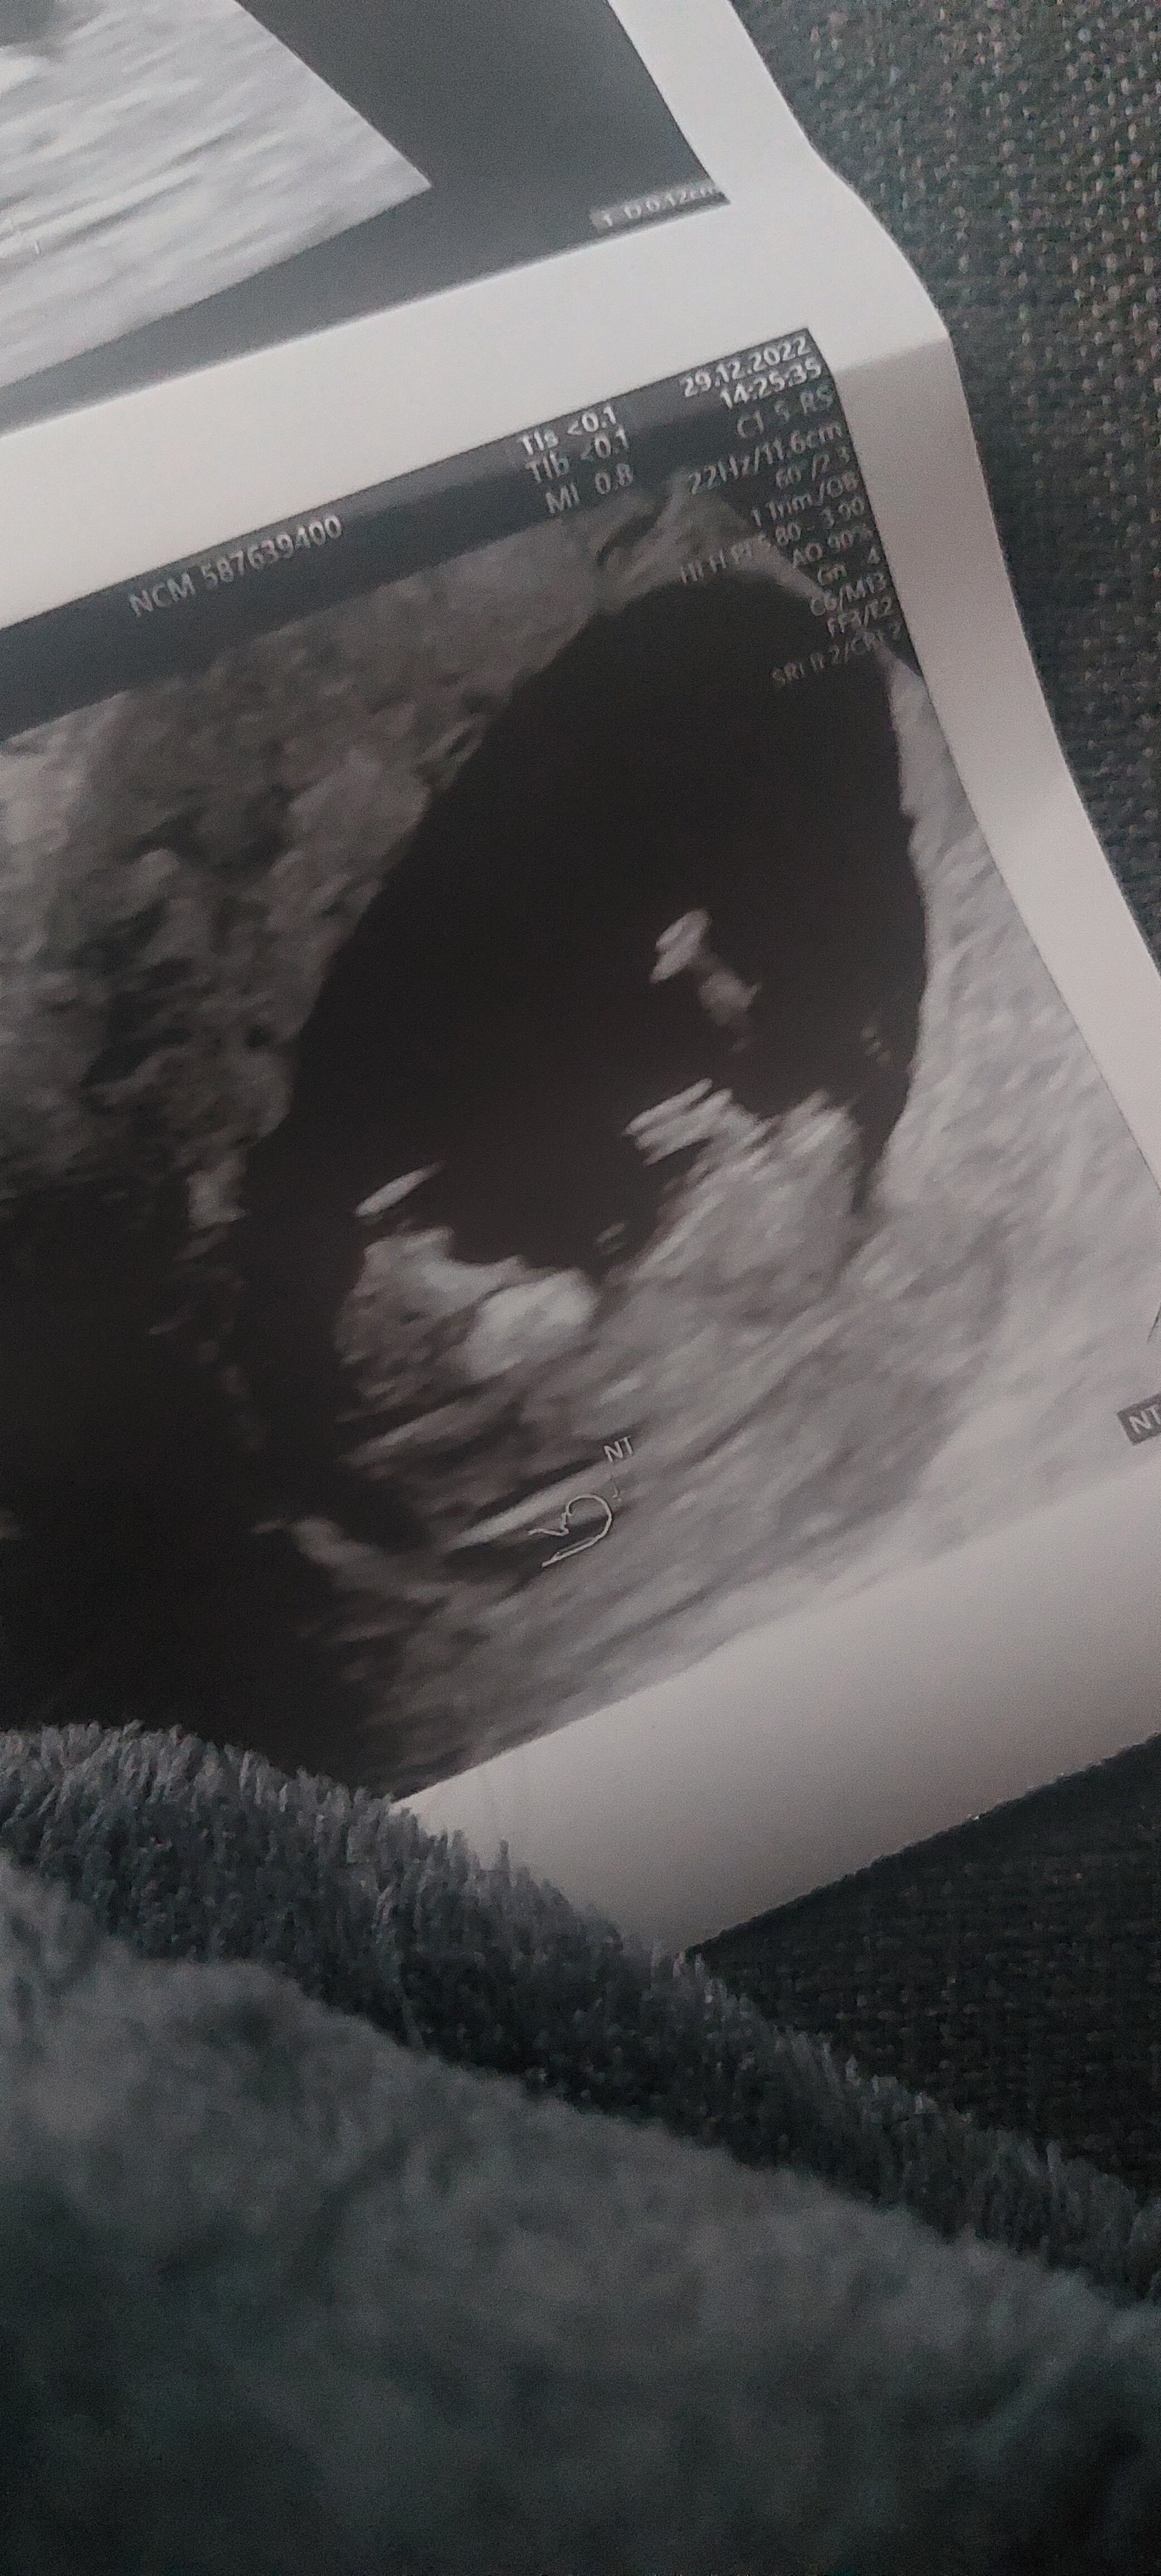

Udało mi się dostać na wizytę, warto było czekać 5h pod gabinetem, bo pani doktor super i zwróciła uwagę na rzeczy, na które nie patrzył poprzedni lekarz, np czeka mnie picie tej podobno paskudnej glukozy, bo cos tam nie tak w wynikach. Ale poza tym wszystko w porządku z maluszkiem, kamień z serca 😊 a bejbik w brzuchu skakał jak taka foczka 😂 cudowny widok. Zdjęcie kiepskie, ale jest.

W końcu czuję się zaopiekowana, może będę teraz spokojniejsza 😊

• 20221229_150014.jpg

20221229_150014.jpg

1,6 MB · Wyświetleń: 104